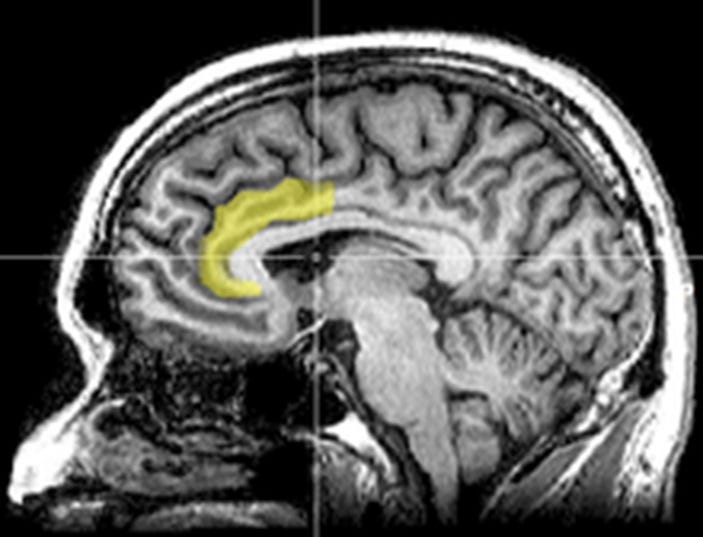

For example, Proceedings of the 2013 National Academy of Sciences suggests that forecasting future criminal behaviour could become a reality in the near future. According to their study, they have found the first evidence that brain scans might be used to both predict who will be likely to commit a crime and also how long it will be before that person commits a crime. This prediction is based on the activity in a region of the brain called the anterior cingulate cortex.

During the scan, subjects were asked to press a button in response to a stimulus on a screen, except when a certain symbol also appeared, in which case they were to refrain from pressing the button. It was found that criminals couldn’t help but press the button either way, and that they were more impulsive than the average person. From these results, it was concluded that the part of their brain responsible for stopping an action may be deficient, that is, once an impulsive person gets started on a criminal action, even if they realise potential negative consequences, they cannot stop themselves.